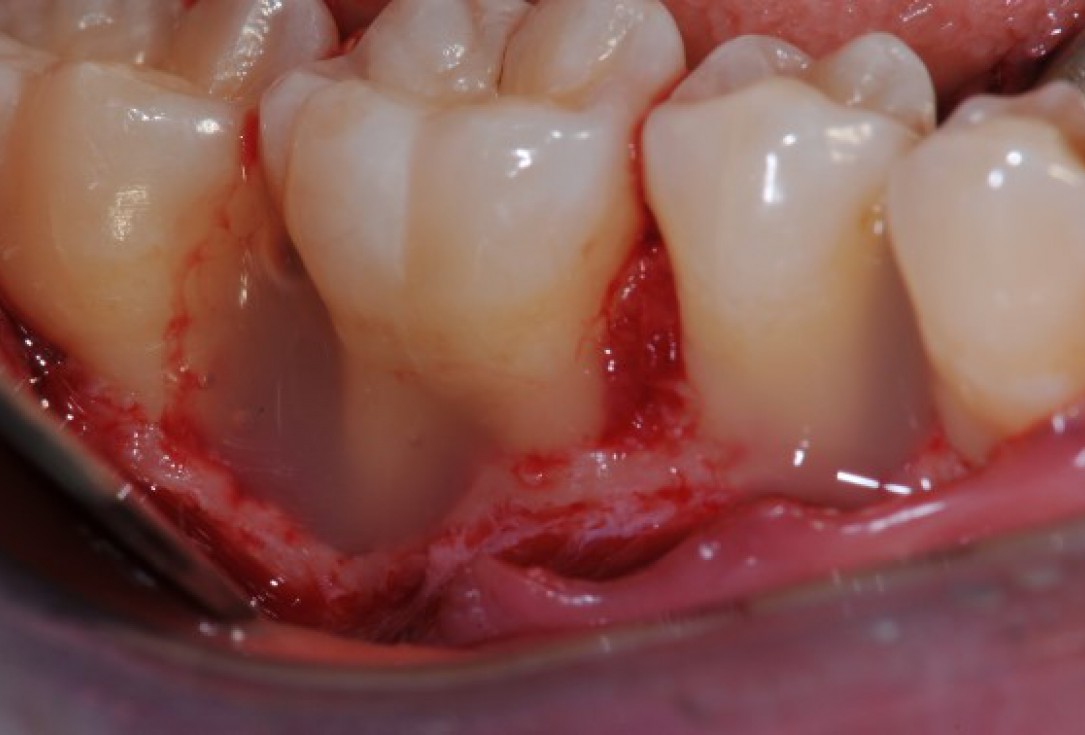

07/22 - Intra-operative view reveals deep non-contained intrabony defects distally to tooth 46 (PPD 10 mm) and on the mesial aspect of tooth 45 (PPD 6 mm). Buccal view.

Deep intrabony defects treated using Straumann® Emdogain® - Dr. M. Stefanini